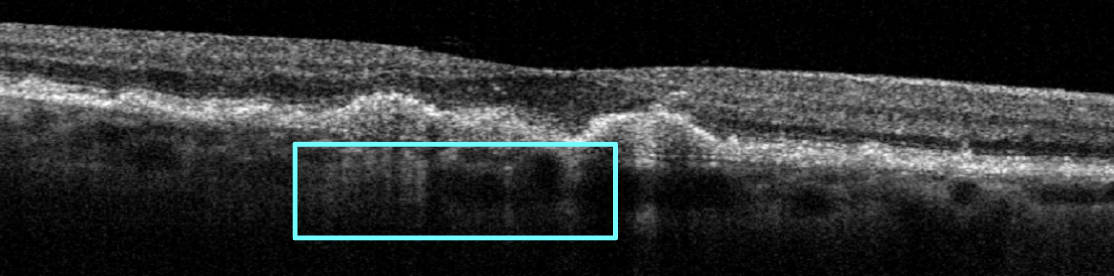

The earliest OCT biomarker for GA is choroidal hypertransmission defects—bright columns extending under the retina and into the choroid due to a compromised RPE (see Figure 2). This structural change on OCT can be observed before visible retina atrophy, making it a crucial early warning sign that should prompt clinicians to educate patients and tighten the in-office monitoring schedule.